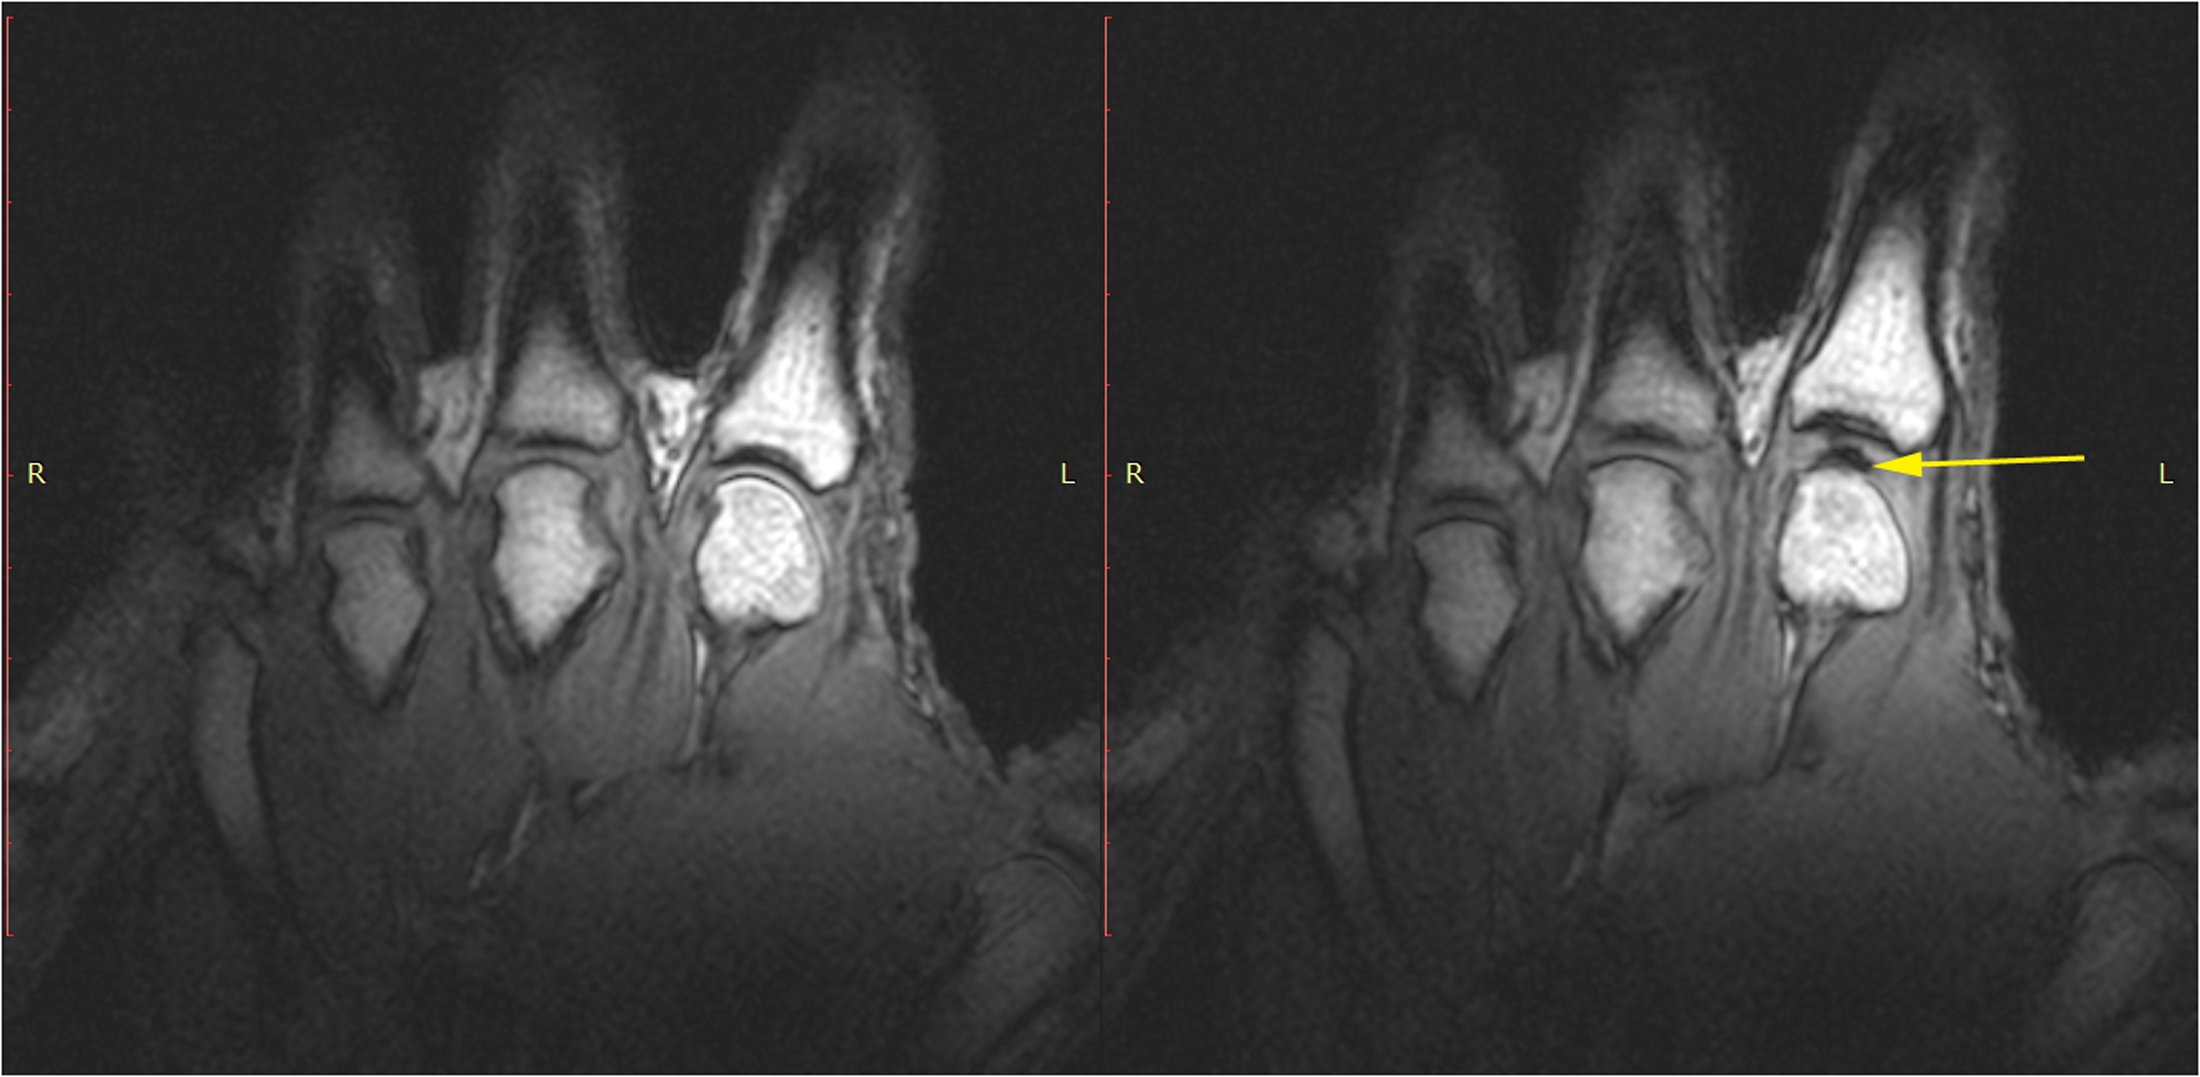

CavitationIRM d’une articulation avant et après le phénomène de Vacuum.  Sur l’image de droite on observer la formation d’une cavité au bout de la flèche jaune.  Source: Plos One, Real-Time Visualisation of Joint Cavitation.  Pour voir la vidéo sur Youtube: https://www.youtube.com/watch?v=_ZNENkkf5Uw

L’ajustement chiropratique entraîne un étirement très rapide de la capsule articulaire au-delà de la limite physiologique normale, ce qui augmente le volume de la capsule et crée un « vacuum » ou une pression négative à l’intérieur de l’articulation.  Le terme précis pour nommer ce phénomène est la cavitation, mais pour faire une image, on peut l’appeler la « bulle ».  L’oxygène, le dioxyde de carbone et l’azote dissous dans le liquide synovial passent de la forme liquide à la forme gazeuse, remplissant ainsi le vide. On pourrait comparer cela à l’ouverture d’une bouteille de champagne. Au moment où la bouteille s’ouvre, les gaz dissous dans le liquide s’échappent. On aperçoit alors les bulles remonter à la surface.

Si les scientifiques s’entendent sur la formation de la « bulle », il existe toutefois deux théories expliquant l’origine du son, qui se font bataille depuis plusieurs décennies. La première veut que ce soit l’éclatement de la bulle (ou de microbulles de gaz) qui entraîne le « crac » sonore alors que l’autre soutient que c’est plutôt la formation de la bulle qui produirait le bruit typique. Deux études plus récentes (2015 et 2018), une démontrant la cavitation sous résonance magnétique et l’autre présentant plutôt un modèle mathématique, ont gardé les deux théories sur le tapis.